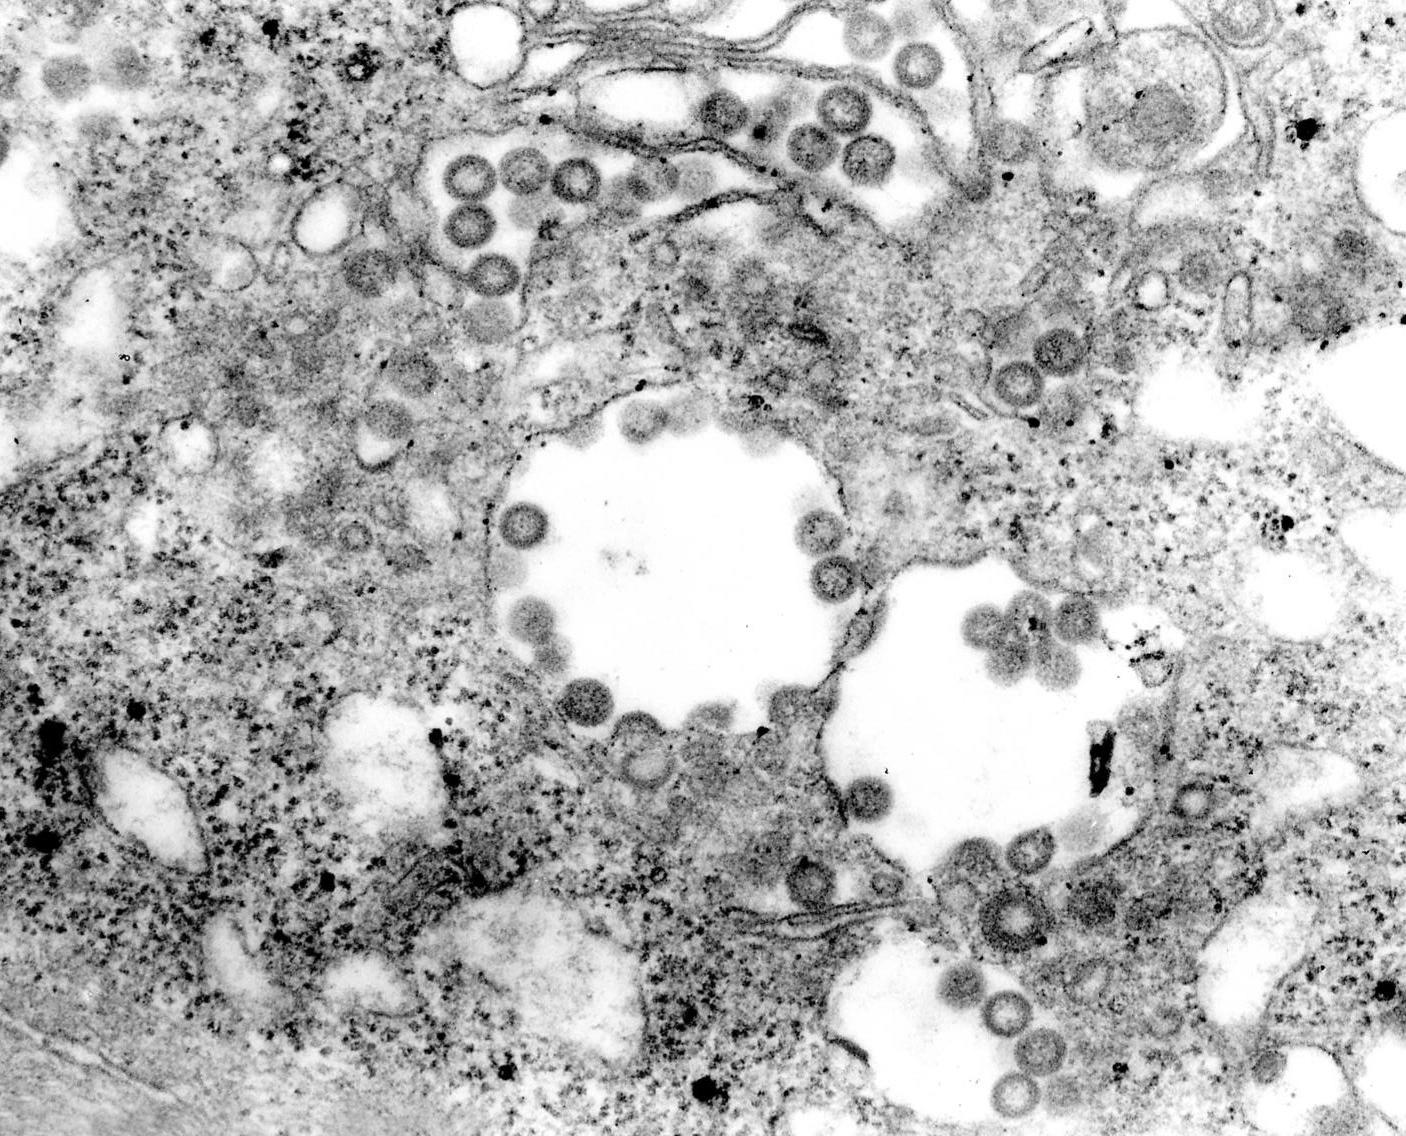

RVFV belongs to the Bunyaviridae family within the genus Phlebovirus

It is an enveloped virus containing a capsid and single-stranded RNA genome.